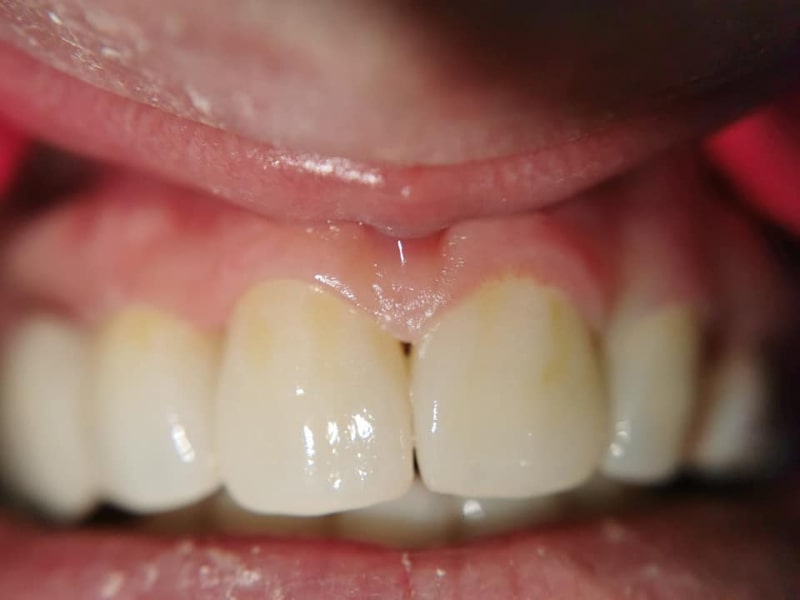

Punte Ceramică